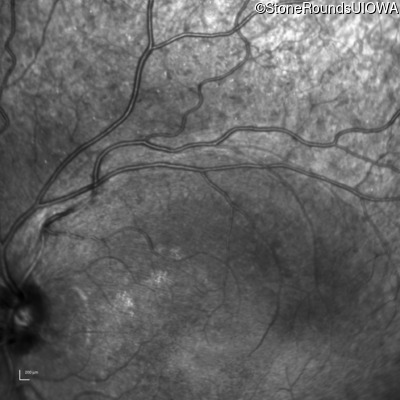

Infrared Fundus Photograph - Right - 20/25 -1

Exemplar